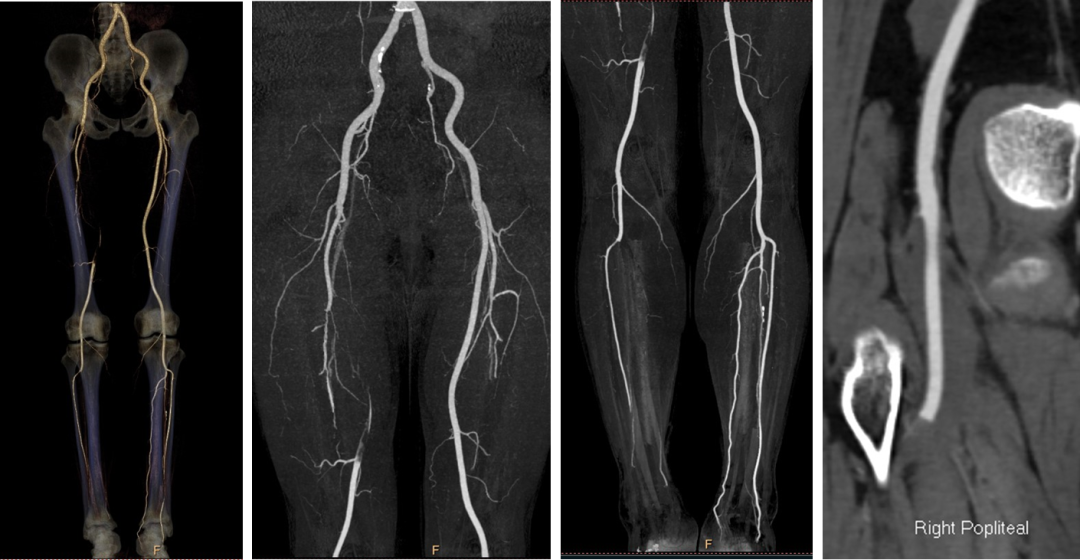

术前CTA